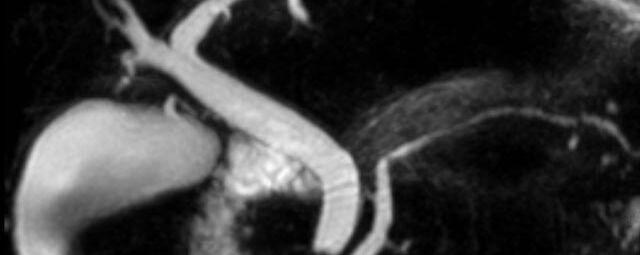

MR-Angiografie (MRA)

• MR-Angiografie ohne Kontrastmittel

• Time of Flight (TOF)-Angiographie

Je nach Fragestellung und Körperregion Gefäßdarstellung ohne Kontrastmittel bei Kontrastmittelunverträglichkeit oder terminaler Niereninsuffizienz möglich.

• MR-Angiographie mit Kontrastmittel

• Erfassung arterieller und venöser Gefäße/Bypässe aller Körperregionen mit 3D-Rekonstruktion